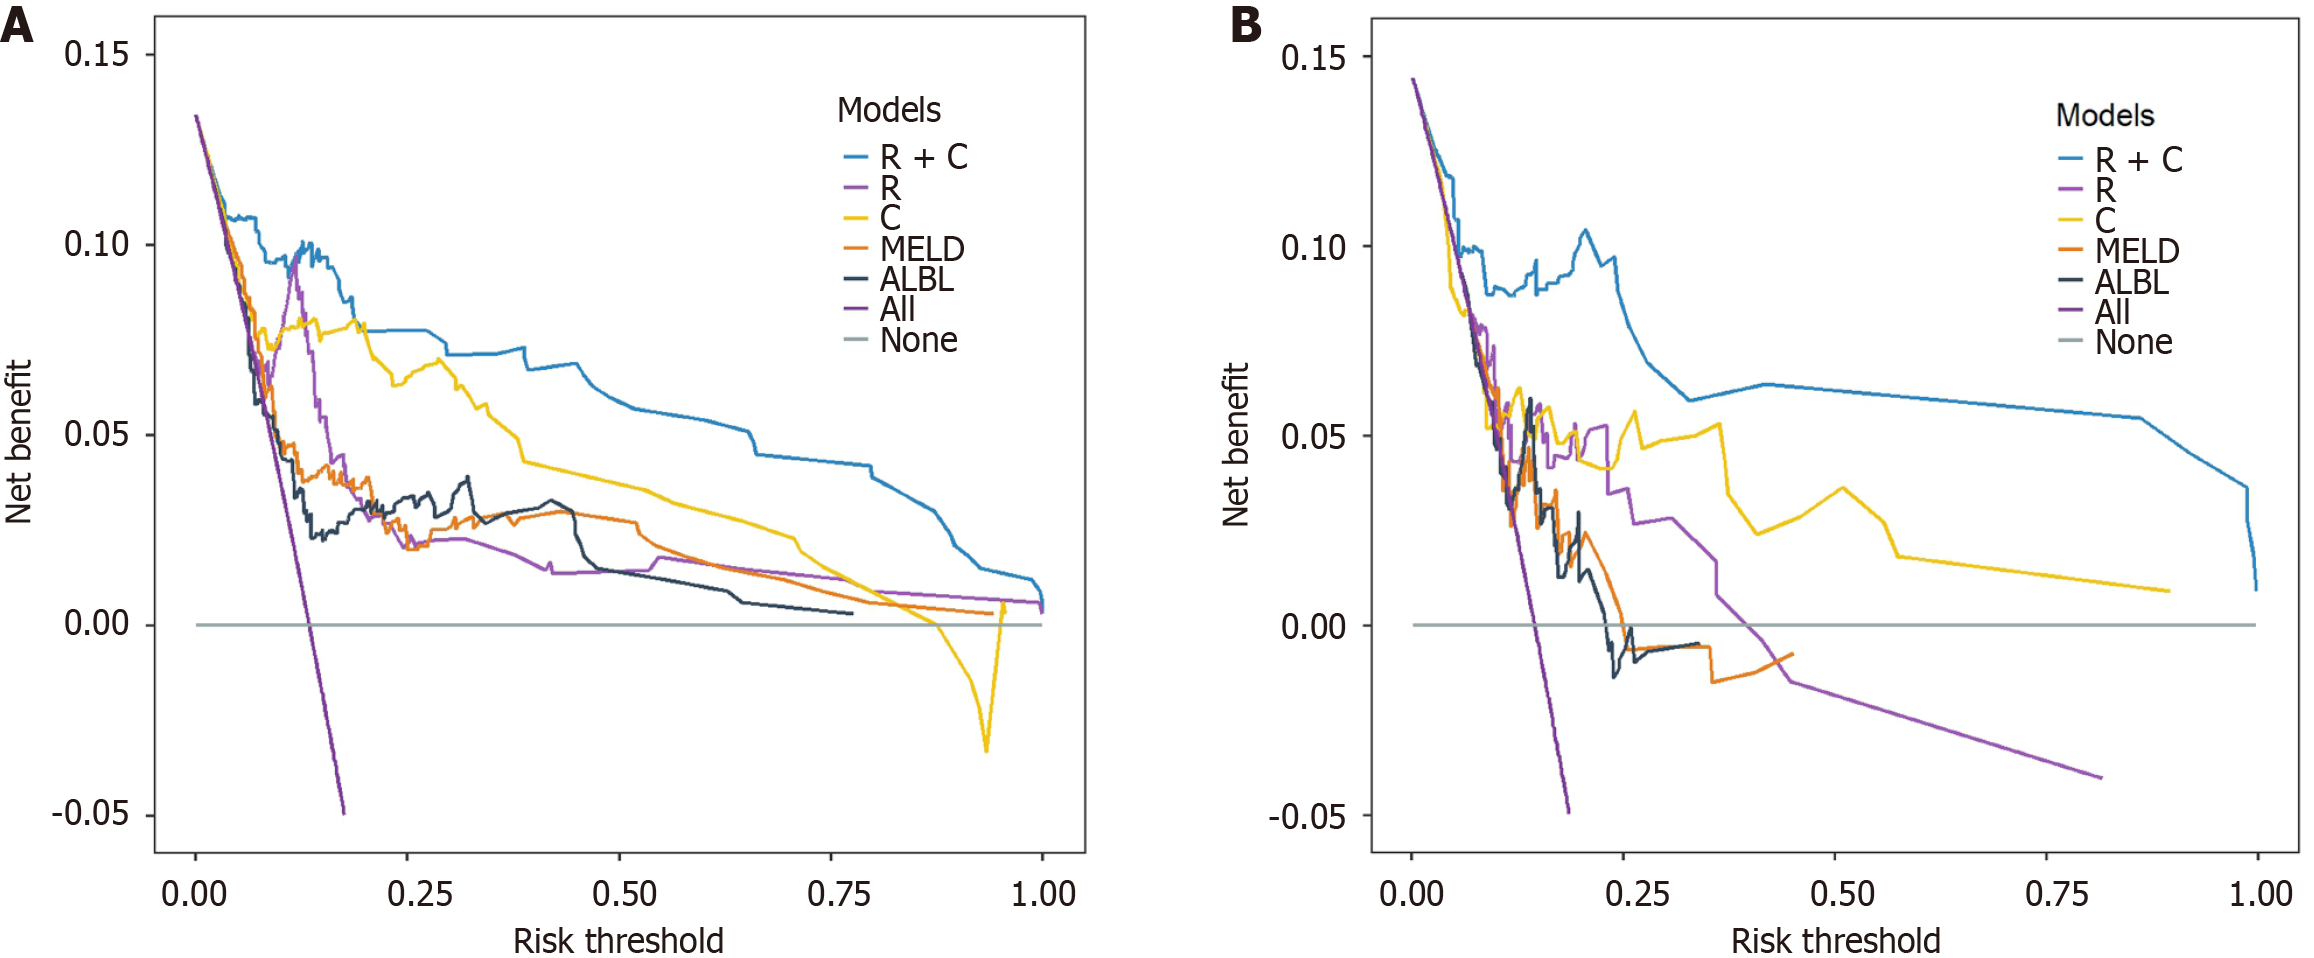

The Radscore comprised four hepatic and six splenic CT features, which predicted the risk of variceal bleeding. Multivariate analysis identified invasive treatment to relieve hepatic venous outflow obstruction, anticoagulant therapy, and hemoglobin levels as independent clinical predictors. The R + C model achieved C-indices of 0.906 (training) and 0.859 (validation), outperforming the radiomics and clinical models alone (AUC: training 0.936 vs 0.845 vs 0.823; validation 0.876 vs 0.712 vs 0.713). DCA showed higher clinical net benefit across the thresholds. The model stratified patients into low-, medium- and high-risk groups with significant differences in bleeding rates (P < 0.001). An online tool is available at https://bcsvh.shinyapps.io/BCS_Variceal_Bleeding_Risk_Tool/.

To construct a comprehensive risk prediction model, the radiomics-based Radscore was integrated with significant clinical variables identified through multivariate Cox regression analysis. The final model revealed that the following were independent risk factors for bleeding in patients with BCS. Invasive treatment to relieve hepatic venous outflow obstruction [hazard ratio (HR) = 0.089, 95%CI = 0.044-0.181, P < 0.001), use of anticoagulants (HR = 10.653, 95%CI = 3.102-36.582, P < 0.001), gender (HR = 2.332, 95%CI = 1.057-5.144, P = 0.036), platelet count (HR = 0.992, 95%CI = 0.984-0.999, P = 0.035), and Radscore (HR = 1.545, 95%CI = 1.236-1.932, P < 0.001). These variables were incorporated into a nomogram for individualized prediction (Figure 4). The predictive accuracy of the radiomics + clinical (R + C) model was assessed using the C-index, which achieved values of 0.906 in the training set and 0.859 in the validation set, indicating excellent discrimination. The R + C model demonstrated better predictive performance compared to the clinical-only model (C model) and the radiomics-only model (Radscore; Table 4). ROC curves were generated to assess model discrimination over a 3-year follow-up period. The results showed that the R + C model achieved superior discrimination compared to the individual Radscore and C model, as reflected by its larger AUC in both the training and validation datasets (Figure 5). Calibration curves confirmed a strong alignment between predicted and observed outcomes (Figure 6), while DCA demonstrated the superior net clinical benefit of the R + C model across a wide range of threshold probabilities (Figure 7).